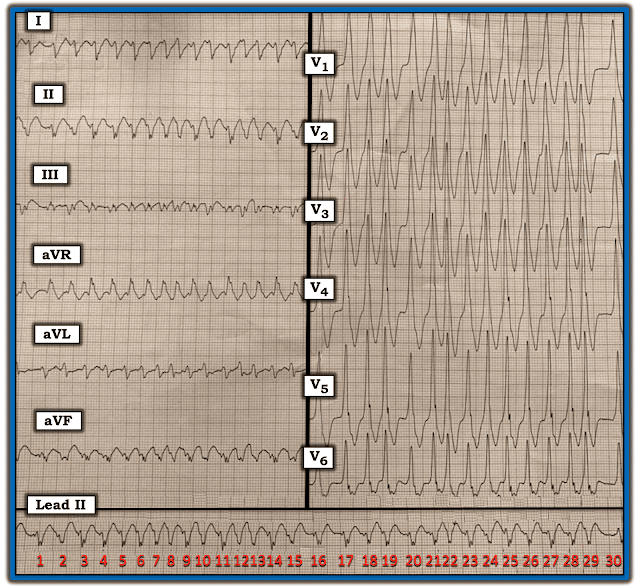

ЭКГ на рис. 1 принадлежит 50-летнему мужчине, который поступил в отделение неотложной помощи с частым сердцебиением.

Рисунок 1: Исходная ЭКГ 50-летнего мужчины, поступившего в отделение неотложной помощи с частым сердцебиением.

Мое непосредственное впечатление от ЭКГ на рис. 1 (сформировавшееся в течение первых 2-3 секунд просмотра этой записи) — ритм очень быстрый, а комплекс QRS явно широкий.

- Ритм на рисунке 1 быстрый, но не регулярный. Внимательно посмотрите на длинную полосу ритма II отведения (рис. 2) — ритм нерегулярно нерегулярный (т. е. интервалы R-R варьируются от одного удара к другому).

- Зубцы P отсутствуют.

- Очевидно, что комплекс QRS широкий (т. е. если посмотреть на те отведения, в которых комплекс QRS выглядит самым широким, не должно быть никаких сомнений в том, что продолжительность комплекса QRS составляет не менее 3 маленьких прямоугольников = более 0,12 с).

ЖЕМЧУЖИНА №1: Очевидно, что частота этой нерегулярной тахикардии очень высока. Уместно (как мы сейчас увидим) определить, насколько быстрым является ритм в его самой быстрой точке.

- Самые короткие интервалы R-R - между комплексами № 7-8; 12-13; и № 21-22 — длительностью чуть более 1 большой клетки для этих 3 интервалов. Это соответствует максимальной частоте желудочков более 250 в минуту!

- Мы можем рассчитать среднюю частоту для этой нерегулярной тахикардии, отметив, что в этой 9-секундной полосе ритма 30 ударов (т. е. полоса ритма — это 45 больших клеток ÷ 5 = 9 секунд). Это соответствует средней частоте желудочков ~ 200 в минуту!

Рисунок 2: Я пронумеровал комплексы в длинной полосе ритма II отведения.

Ритм на рис. 2 чрезвычайно быстрый и нерегулярно нерегулярный. Предсердной активности не наблюдается. Хотя комплекс QRS явно расширен, грубая нерегулярность ритма делает желудочковую тахикардию маловероятной. Это оставляет ФП (фибрилляцию предсердий) в качестве вероятного диагноза. Тем не менее, частота ритма в определенных точках записи намного выше, чем обычно наблюдается при мерцательной аритмии.

- В норме при ФП рефрактерный период АВ-узла не позволяет проводить к желудочкам более 150-200 импульсов в минуту. Желудочковый ответ, частота которого иногда превышает 250 в минуту, просто слишком быстр для передачи предсердных импульсов по нормальному (АВ-узловому) пути проведения.

ЖЕМЧУЖИНА № 2: Признание того, что фибрилляция предсердий с широким комплексом QRS приводит к желудочковому ответу, который часто превышает 220 в минуту (а иногда превышает 250 в минуту) — немедленно говорит вам, что у пациента должен быть синдром WPW (Вольфа-Паркинсона-Уайта), при котором импульсы ФП обходят АВ-узел и проводятся к желудочкам через ДПП (добавочный проводящий путь).

- ЖЕМЧУЖИНА № 3: В дополнение к чрезмерно быстрому желудочковому ответу — 2 других характерных ЭКГ-признака ФП у пациента с WPW видны на рисунке 2. К ним относятся: i) имеется удивительная вариация интервалов R-R, при которой некоторые из более длинных интервалов R-R более чем в два раза длиннее самых коротких интервалов R-R (т.е. это происходит для последнего интервала R-R на записи между комплексами № 29- 30); и, ii) В отличие от мономорфной ЖТ - морфология комплекса QRS показывает некоторые неожиданные изменения (т. е. комплексы № 2, 8, 12, 13 в длинной полосе ритма II отведения не имеют отчетливой засечки, наблюдаемой в других комплексах).

- Риск развития ФЖ во время ФПу пациента с WPW значительно увеличивается, когда SPERRI (Shortest Pre-Excited R-R Interval - кратчайший интервал R-R предвозбуждения) сокращается до 220-250 мс. Это соответствует кратчайшему интервалу R-R, который по продолжительности едва превышает одну большую клетку, что, по сути, и наблюдается для интервалов R-R между комплексами № 7-8; 9-10; 12-13; 21-22; и 28-29 на рис. 2. Учитывая этот высокий риск ухудшения до ФЖ для WPW-ассоциированной аритмии в сегодняшнем случае — срочная кардиоверсия и направление к электрофизиологу (для катетерной аблации ДПП) четко показаны!